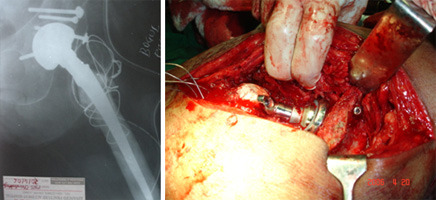

COMPLEX HIP RECONSTRUCTIONS

UNCEMENTED HIP REPLACEMENT

CEMENTED HIP REPLACEMENT